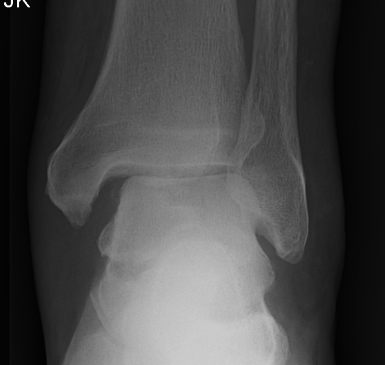

Fracture patterns

| Lateral malleolar fractures | Medial malleolar fractures | Bimalleolar fractures | Trimalleolar fractures |

Weber A - below syndesmosis Weber B - at syndesmosis Weber C - above syndesmosis |

Uncommon |

Fibular + medial malleolus Bimalleolar equivalent - fibular + deltoid ligament Fibular + posterior malleolus |

Fibular fracture + Medial malleolus fracture + Posterior malleolus fracture |